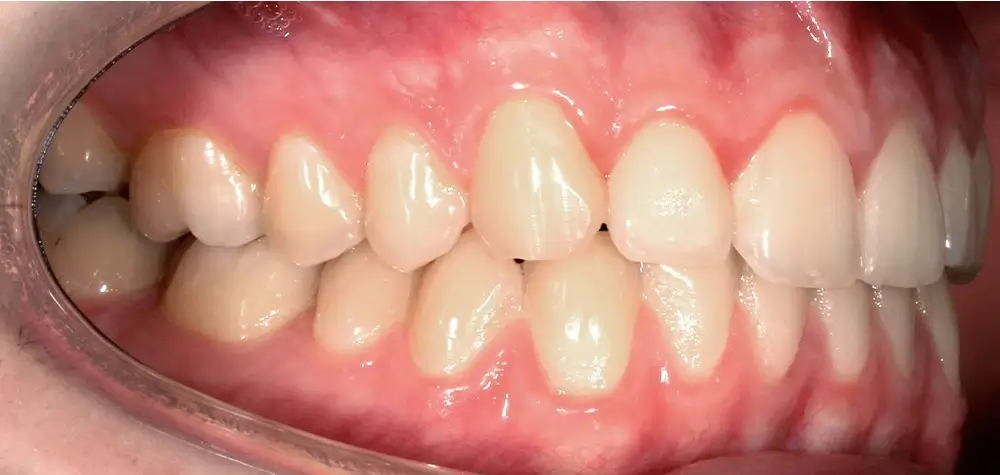

Скученность - Кейс 25

Эффективность устранения дефекта прикуса посредством элайнеров FlexiLigner.

Результаты лечения